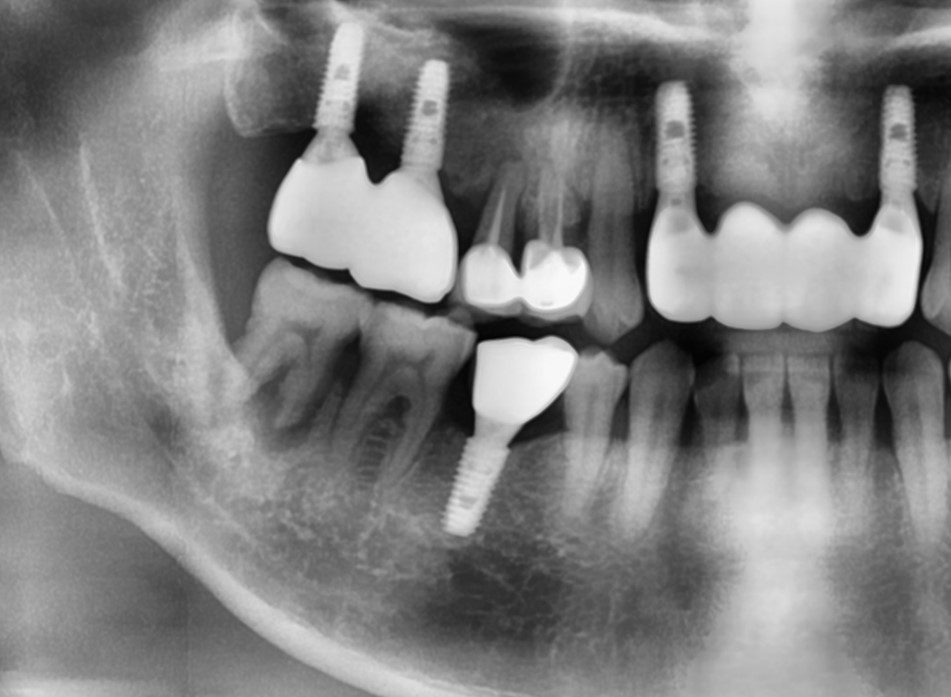

▲8 years after restoration.